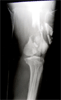

Pre

Op

Later,treated with acute shortening and stabilsation wit Ilizarove fixator for chronic osteomyelitis